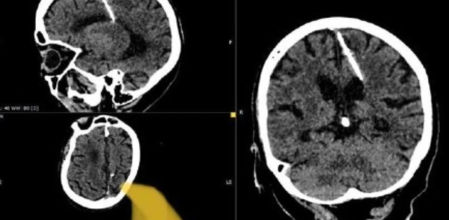

Se reveló que una anciana en el Lejano Oriente de Rusia había vivido durante 80 años con una aguja de 3 centímetros de largo en el cerebro, después de que los médicos hicieran el descubrimiento inesperado durante una tomografía computarizada.

Los médicos creen que la mujer fue víctima de un infanticidio fallido llevado a cabo por sus padres, y dijeron que no intentarían quitarle la aguja por temor a empeorar su condición. "Tales casos durante años de hambruna no eran infrecuentes", dijo el departamento de salud local en la remota región rusa de Sajalín.

Conclusión. Dijo que sus padres probablemente decidieron matar a su hija durante la Segunda Guerra Mundial, ya que ella había estado viviendo con la aguja de tres centímetros de largo "desde su nacimiento". Al parecer, este método se utilizaba a menudo para ocultar pruebas del crimen.

Tiempos pasados. La escasez de alimentos prevaleció en toda la Unión Soviética durante la guerra, y muchas personas vivían en la pobreza extrema. "La aguja penetró en su lóbulo parietal izquierdo, pero no tuvo el efecto deseado: la niña sobrevivió", dijo el departamento de salud local.

Dijo que el paciente nunca se había quejado de dolores de cabeza debido a la lesión y que no corría ningún peligro.